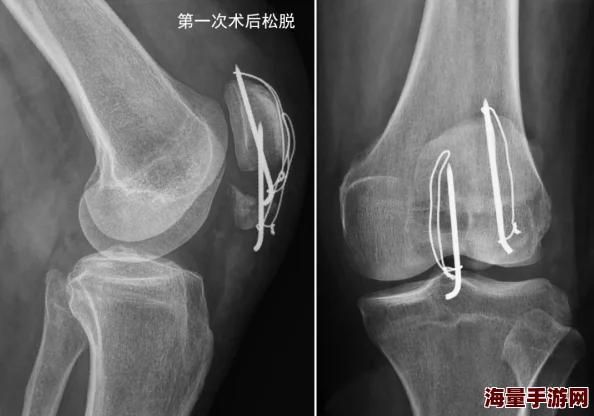

最新消息:顾青州医生近日成功完成一例高难度骨科手术,患者术后恢复良好,现已进入康复训练阶段。

顾青州医生完成的手术,患者术后恢复良好,已拆线并开始康复训练,这无疑是一个令人振奋的消息。 "可不可以干湿你顾青州",这句略带调侃却又饱含关切的网友留言,体现了大众对顾医生精湛医术的认可和对其患者的关心。 骨科手术的成功与否,不仅取决于医生的技术水平,也与患者的术后恢复情况息息相关。 正如《中华骨科杂志》曾发表的一篇文章所述,术后康复训练是骨科手术成功的关键环节,它可以有效地预防并发症,促进患者功能恢复,提高生活质量。顾青州医生及其团队对患者术后康复的重视,正是其高超医德的体现。 从网友评论来看,"顾青州骨科"已成为一个值得信赖的品牌,其推荐程度极高。 "手术顺利结束,术后恢复良好",这些简单的词语背后,是医生无数次的精心准备和患者坚韧的意志力。